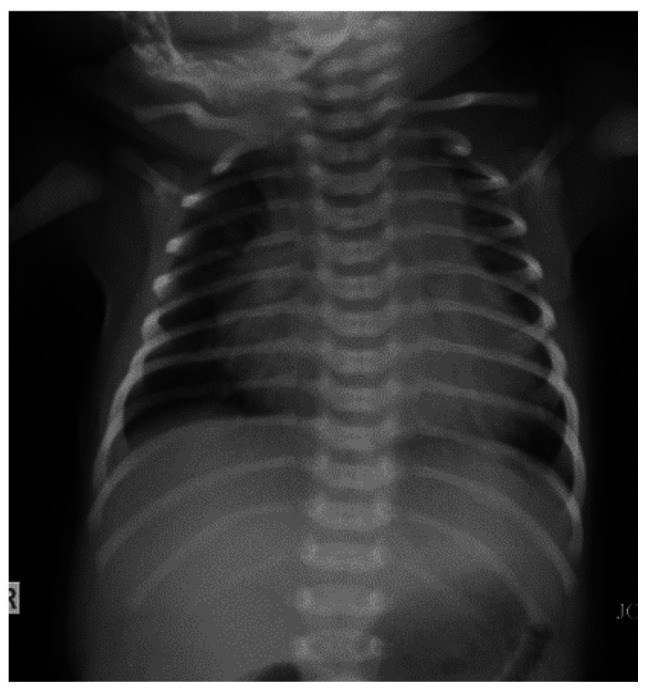

In this article, we present a neonate with the vein of Galen aneurysmal malformation, a rare blood vessel malformation of the brain, which was clinically manifested by signs of cardiac failure. Cranial ultrasound suspected the existence of the vein of Galen aneurysmal malformation, and the diagnosis was confirmed by computed tomography and magnetic resonance imaging. Based on our case, we believe that cranial ultrasound should be included in the screening protocol for neonates with cardiac failure. In addition, we believe that endovascular embolization of the blood vessels that supply the aneurysm is the method of choice in treating the vein of Galen aneurysmal malformation. Treatment of neonates with the vein of Galen aneurysmal malformation is challenging and requires a multidisciplinary approach (neonatologists, cardiologists, neuroradiologists, and neurosurgeons).